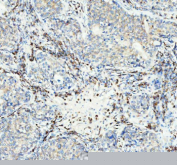

Immunohistochemical staining of Neurokinin 1 Receptor using anti-NKR1 antibody. Neurokinin 1 Receptor was detected in a paraffin-embedded section of human lung cancer tissue. Heat mediated antigen retrieval was performed in EDTA buffer (pH 8.0, epitope retrieval solution). The tissue section was blocked with 10% goat serum. The tissue section was then incubated with 1:50 rabbit anti-NKR1 antibody overnight at 4oC. Peroxidase Conjugated Goat Anti-rabbit IgG was used as secondary antibody and incubated for 30 minutes at 37oC. The tissue section was developed using an HRP secondary and DAB substrate.